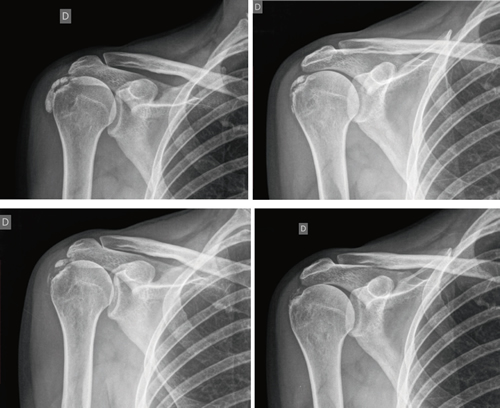

The average number of sessions in our series was 20. The criteria for continuing or stopping treatment was the radiological and clinical evolution (Figures 4 and 5). The interventions were performed up to a maximum of 40 sessions. Perrón treated patients for 9 sessions (3 weekly sessions for 3 weeks) (14). Leduc treated with 10 sessions (3 per week for the first two weeks; then one weekly for 4 weeks) (15). Rioja-Toro treated patients for 40 sessions (5 times per week) and evaluated them at 20 and 40 sessions (3). Chico-Álvarez treated patients between 15 and 30 sessions depending on the radiological evolution (5 times per week) (1).

Fig. 4. 47-year-old female patient with formative right supraspinatus calcific tendinitis who, after 30 sessions of iontophoresis, decreased pain measured by VAS from 6/10 to 3/10 and calcification from 38 mm to 8 mm (assessments at onse and at 10, 20 and 30 sessions, respectively).

Fig. 5. A 44-year-old female patient, with calcific tendinitis of the left supraspinatus, of the resorptive type, who after 20 sessions of iontophoresis decreased pain measured by VAS from 10/10 to 4/10, and calcification from 22 mm to 0 mm (complete disappearance).